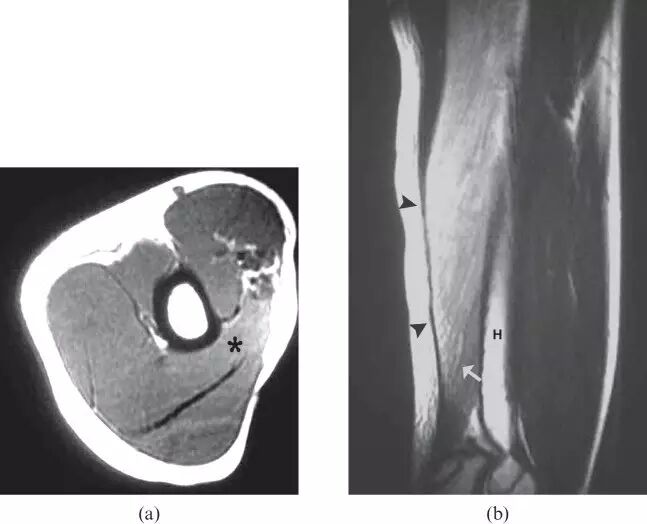

![]()

图5.一名13岁男性的横纹肌溶解症患者,在进行强烈的举重锻炼后,手臂上逐渐出现疼痛。(a)左臂的轴向T1加权的MR图像显示在三头肌肱肌的中间头中微小的增强的信号(星号)。(b)通过上臂的矢状T2加权的MR图像显示肱三头肌(箭头)中的弥散增加的信号强度。注意,水肿样的信号轨迹沿着肌肉束,假设反映肌肉结构的特征性羽毛状外观(箭头)。 相关性肌红蛋白尿证实了左肱三头肌的劳损性横纹肌溶解的诊断。